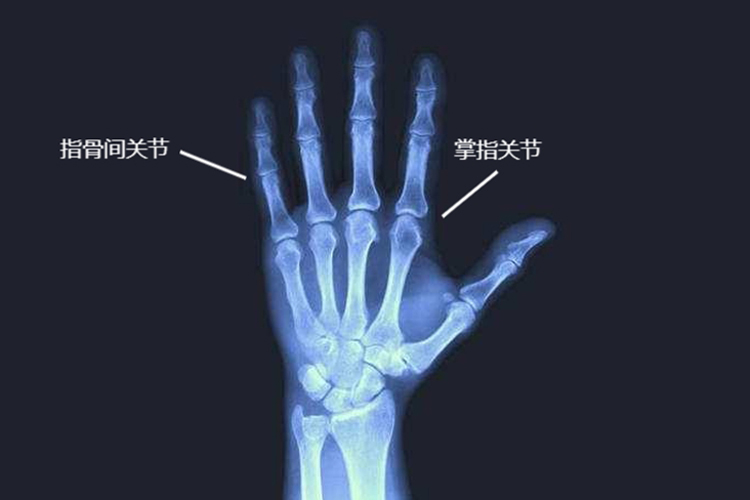

手指关节X光可见5个掌指关节和9个指骨间关节,掌指关节具有屈曲、伸直、外展、内收等作用,指骨间关节与之协同。

手指关节包括掌指关节和指骨间关节。X光可见拇指掌指关节由第1掌骨头及近节指骨底构成,其掌侧有2个籽骨,与近、远侧掌韧带相连;而第2-5指的掌指关节为髁状关节,掌骨头与指骨底的凹陷相关节。指骨间关节包括4个远侧指骨间关节、4个近侧指骨间关节和一个拇指的指骨间关节。

掌指关节为手指的关键性关节,借手的内、外在肌稳定功能,具有屈曲、伸直,以及外展、内收等作用,以发挥手指最有效的功能。而拇指与其他4指指骨间关节的动作皆与掌指关节协同。屈一指骨间关节时,其他指骨间关节与掌指关节也一同屈曲,伸时亦然,如此可以便于工作。